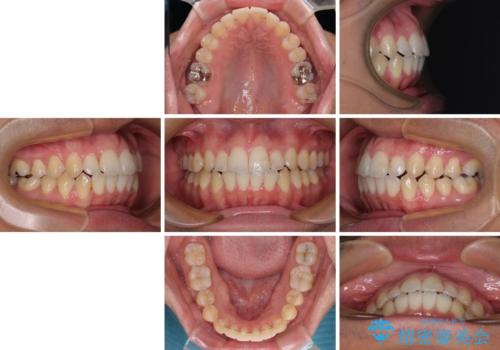

開咬とデコボコを整える インビザライン矯正治療

- 前歯の開咬と叢生を気にして来院された患者様です。

開咬の治療は、前歯を閉じるように動かすとともに、上下臼歯を圧下(骨内にめり込ませる)させることで進めて行きます。

インビザラインは臼歯の圧下を効果的に行えるため、インビザラインを用いて矯正治療を行うこととしました。また、アンカースクリューを用いて、口元の突出感の改善を図りました。